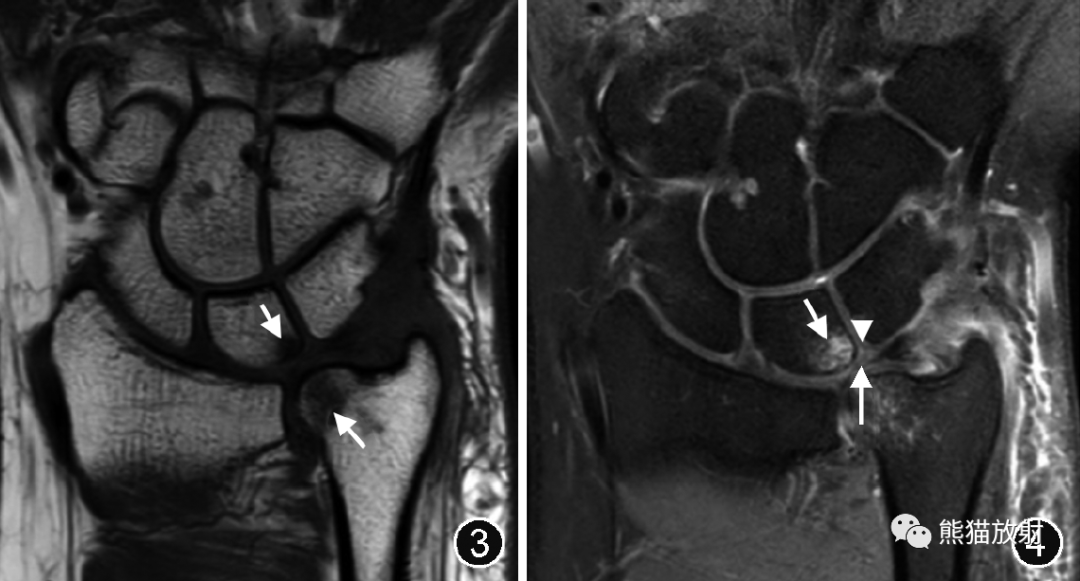

CT可以较X线更清晰地显示细微骨质结构的改变;晚期可见尺腕部骨性关节炎改变。MRI有助于显示隐匿性病变、TFC以及月三角韧带的损伤,典型表现包括月骨近端尺侧面、三角骨近端桡侧面、尺骨头骨髓水肿,关节面硬化、关节软骨缺损、软骨下囊变,TFC形态不规则、变薄、穿孔(图3,4),部分患者可合并月三角韧带撕裂,晚期表现为尺腕部骨性关节炎。

图3,4 尺骨撞击综合征。女,56岁,左腕关节尺侧疼痛。腕关节冠状位T1WI(图3)和质子密度加权脂肪抑制序列图像(图4)示尺骨正向变异,月骨近端尺侧面及尺骨头软骨软化、软骨下骨髓水肿改变(↑);质子密度加权脂肪抑制序列可清晰显示三角纤维软骨明显变薄(图4长↑)以及月三角韧带损伤(图4▲)